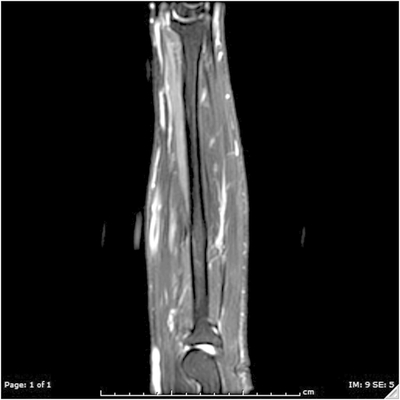

Click on an image below to view more info.